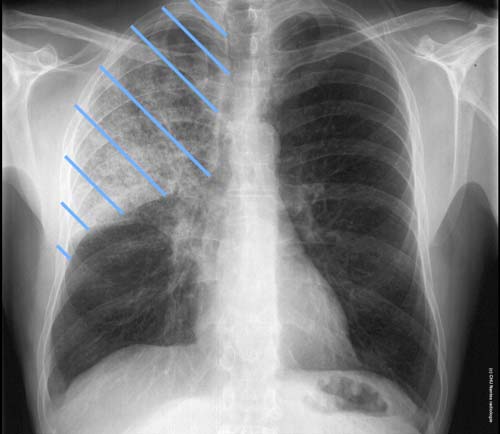

Syndrome interstitiel en rayon de miel

Syndrome interstitiel en rayon de miel du lobe supérieur droit (lymphagite carcinomateuse)